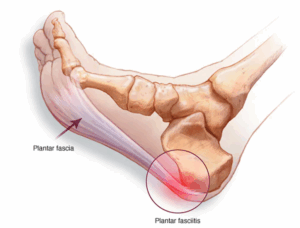

Plantar fasciitis

Plantar fasciitis (PLAN-tur fas-e-I-tis) is one of the most common causes of heel pain. It involves inflammation of a thick band of tissue that runs across the bottom of each foot and connects the heel bone to the toes, known as the plantar fascia.